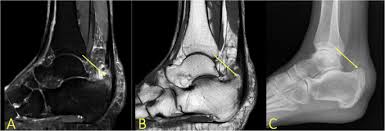

A B Subchondral Bone Marrow Edema Is Seen On Short Tau Inversion Download Scientific Diagram